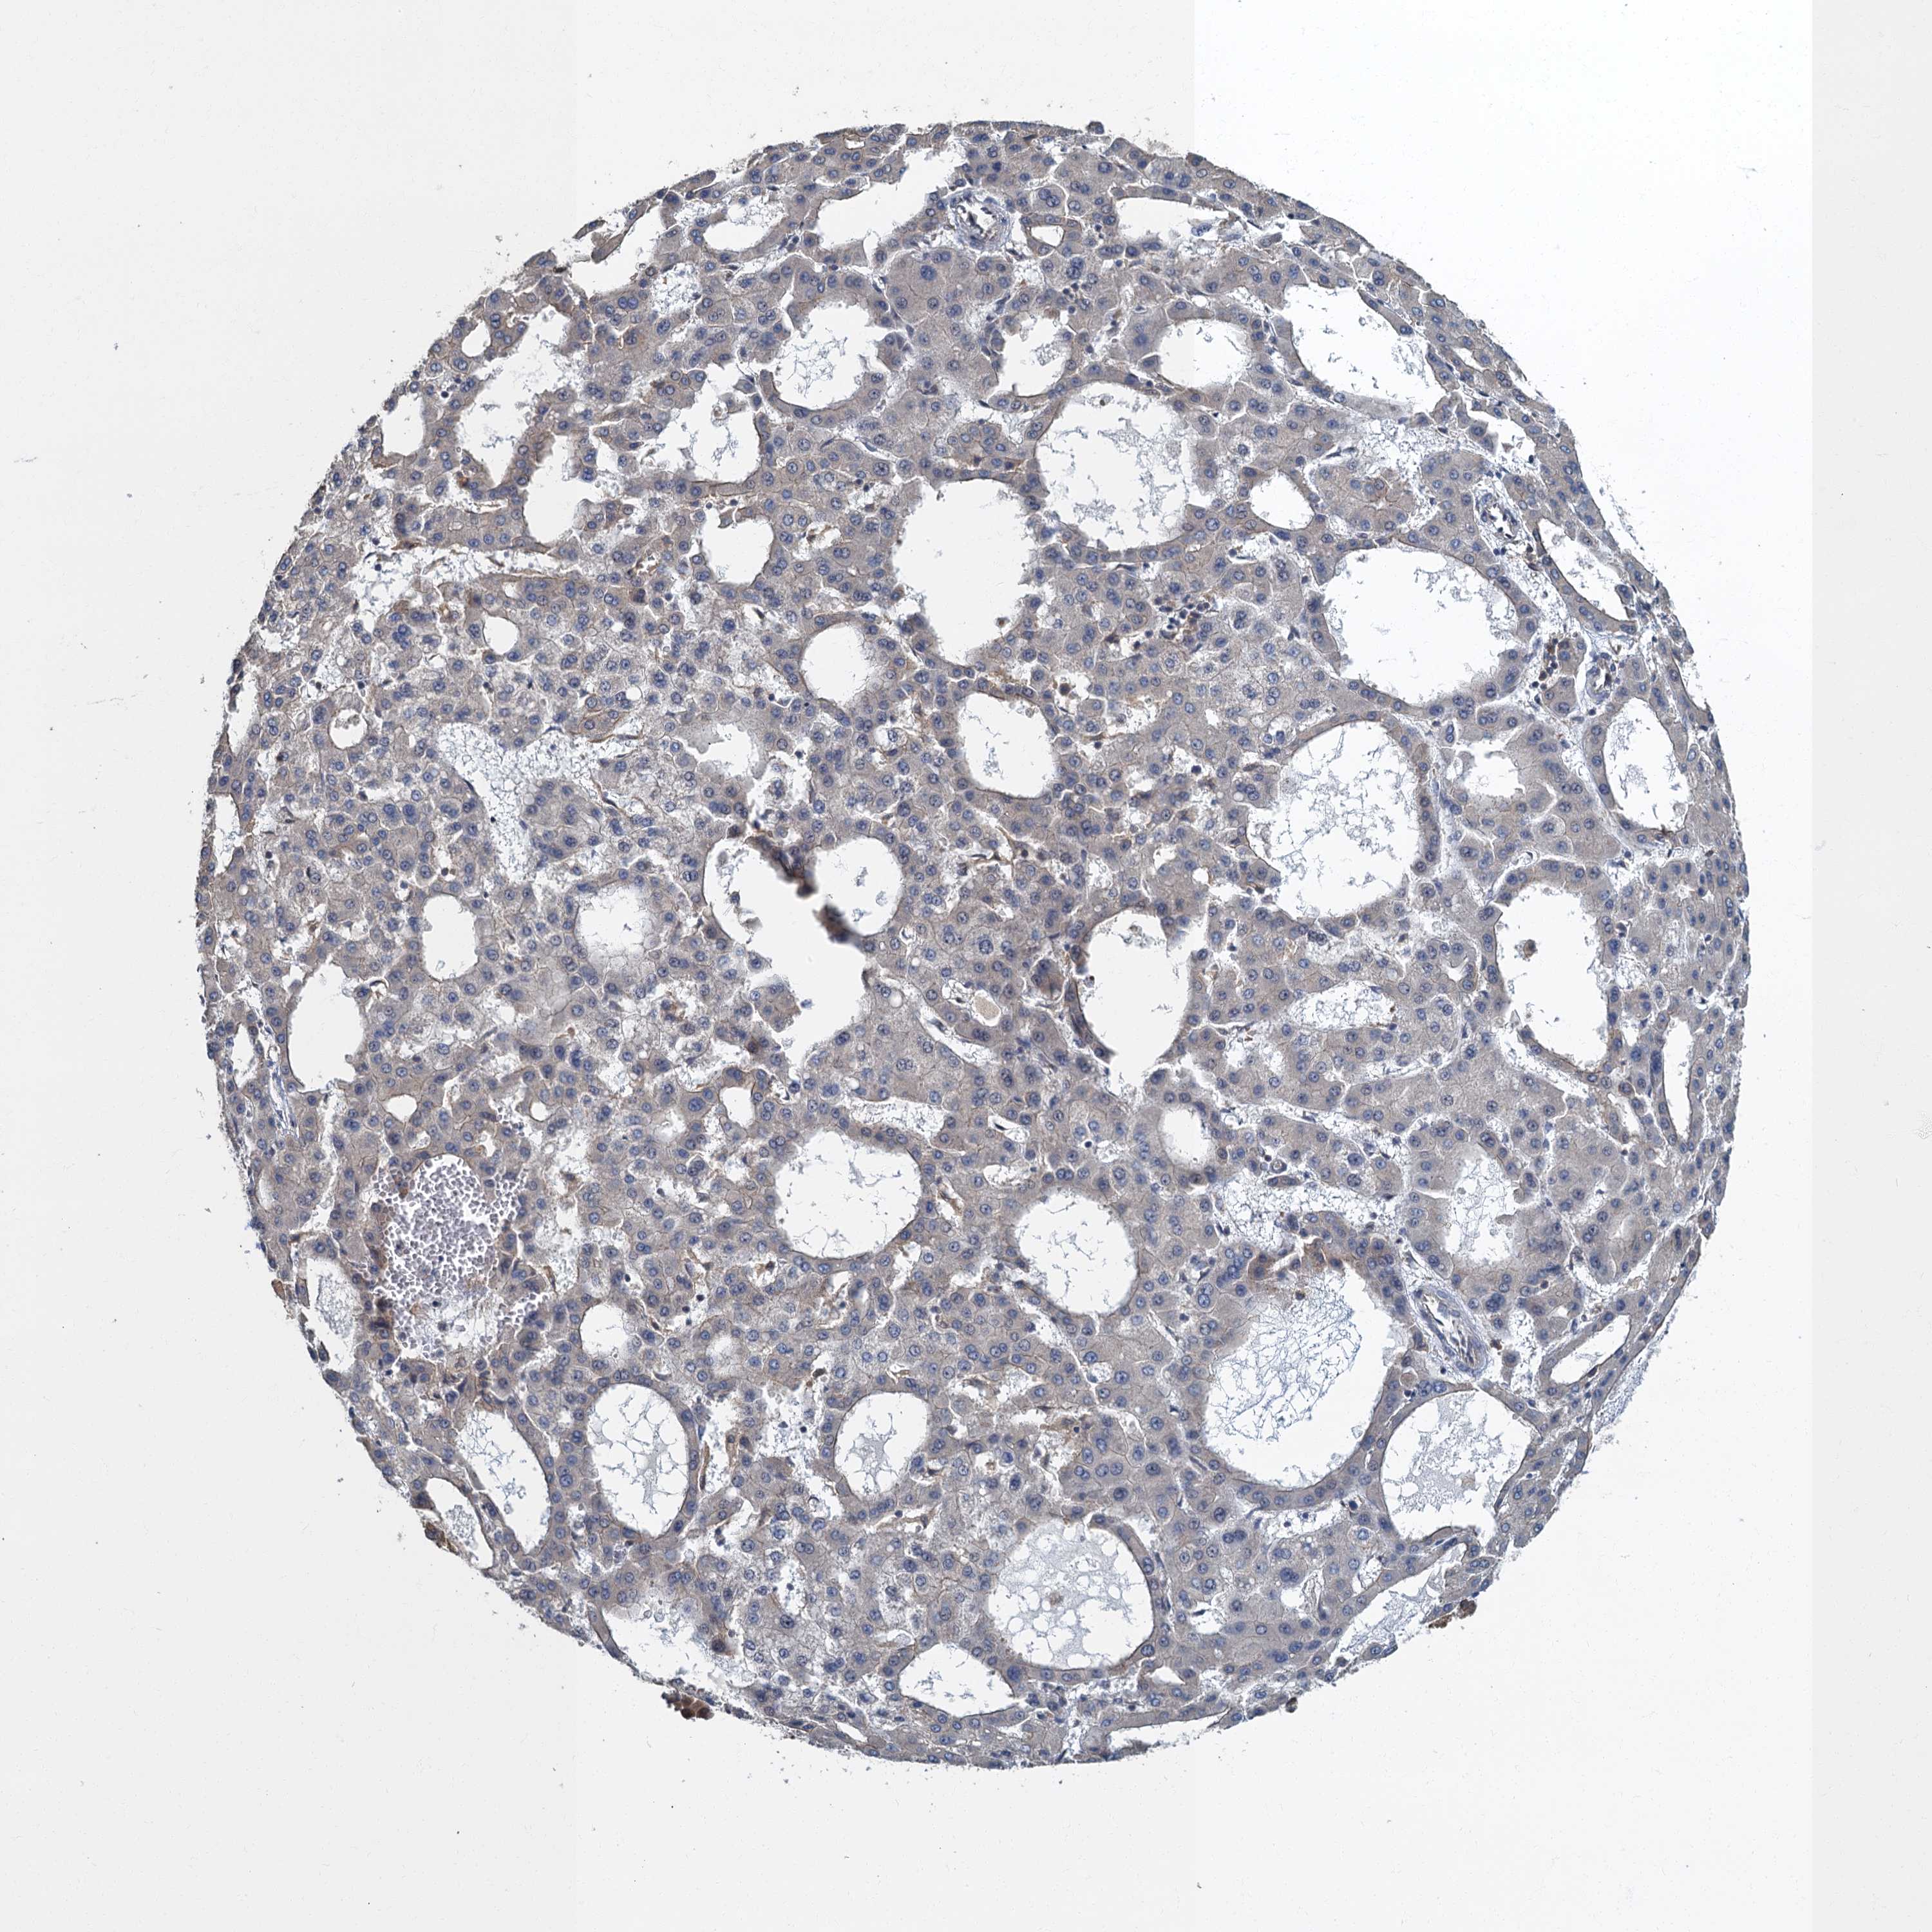

LIVER CANCER - Protein expressioni

A mouse-over function shows sample information and annotation data. Click on an image to view it in a full screen mode. Samples can be filtered based on level of antibody staining by selecting one or several of the following categories: high, medium, low and not detected. The assay and annotation is described here.

Note that samples used for immunohistochemistry by the Human Protein Atlas do not correspond to samples in the TCGA dataset.

Antibody stainingi

Antibody staining in the annotated cell types in the current human tissue is reported as not detected, low, medium, or high, based on conventional immunohistochemistry profiling in selected tissues. This score is based on the combination of the staining intensity and fraction of stained cells.

Each image is clickable and will lead to virtual microscopy that enables deeper exploration of all samples and also displays staining intensity scores, fraction scores and subcellular localization as well as patient and tissue information for each sample.

Antibody HPA039951

Staining

High

Medium

Low

Not detected

Intensity

Strong

Moderate

Weak

Negative

Quantity

>75%

75%-25%

<25%

None

Location

Nuclear

Cytoplasmic/membranous

Cytoplasmic/membranous,nuclear

Cholangiocarcinoma

Carcinoma, Hepatocellular, NOS